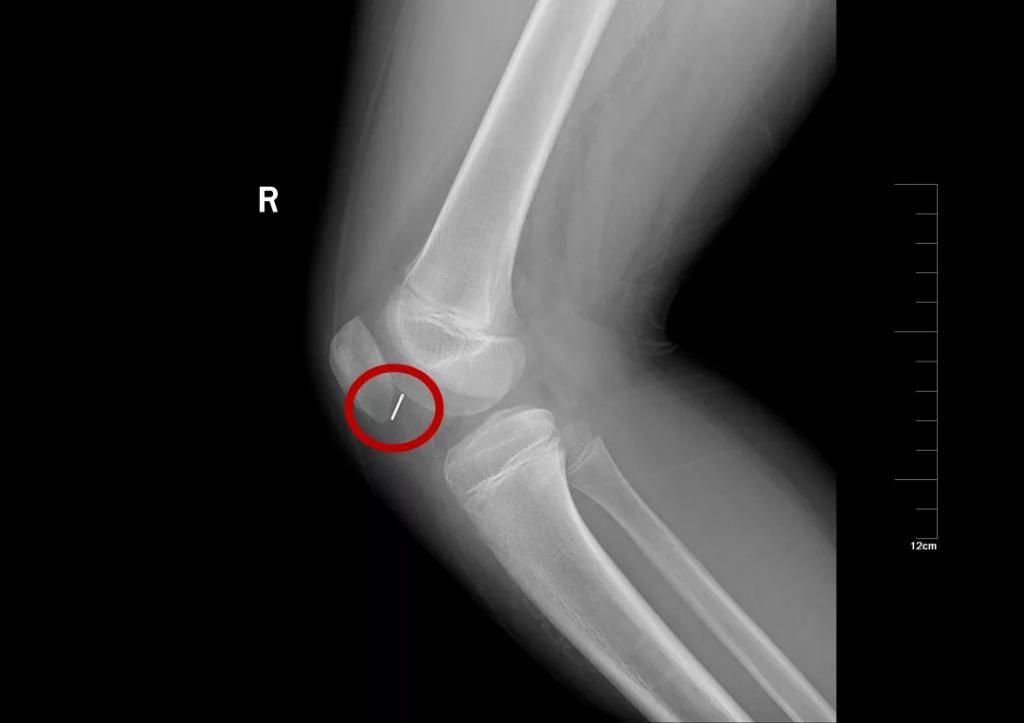

10岁·膝盖异物

半截针

患儿10天前不慎受伤,致半截床套针刺入右膝,无明显疼痛及活动障碍,至当地医院就诊摄片示右膝异物。

文章图片